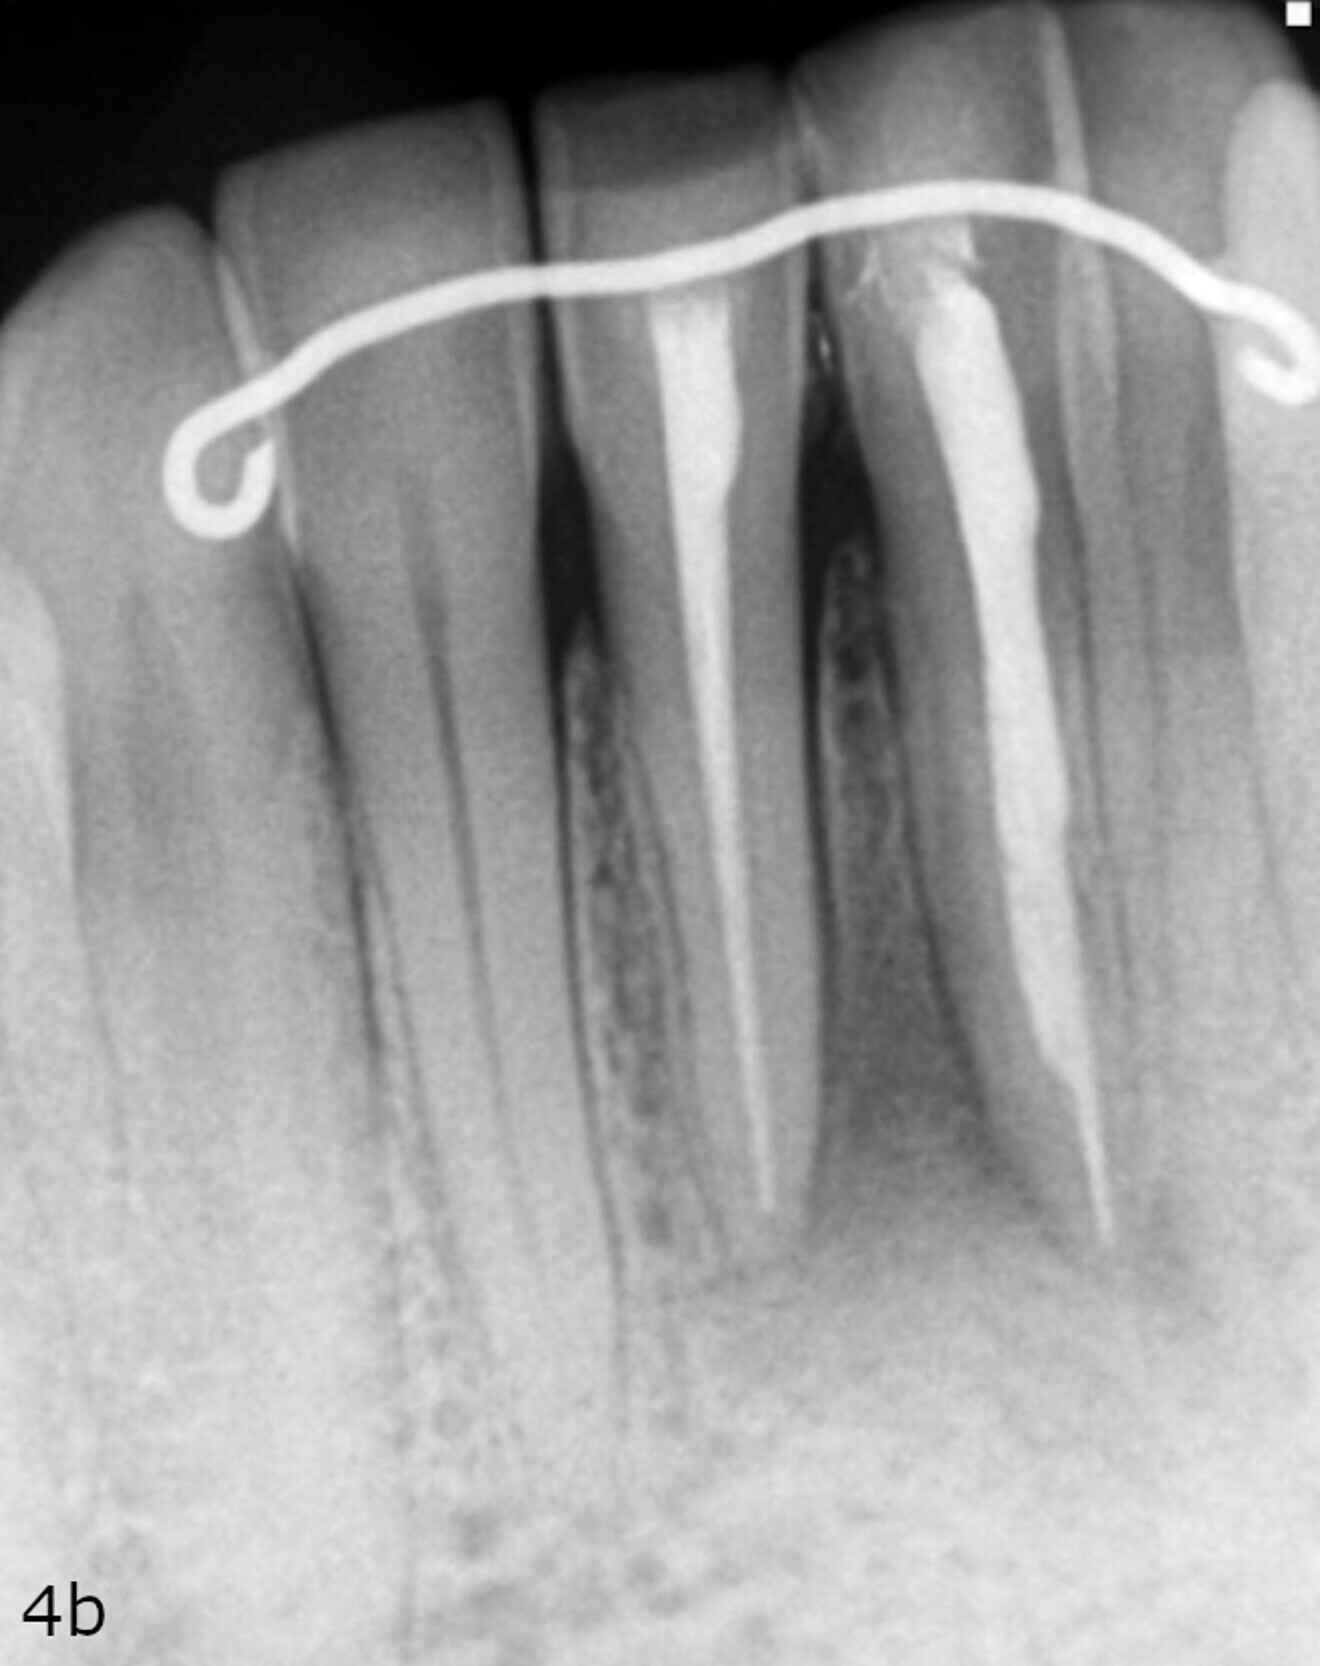

Fig. 4a: Radiographs showing the immediate post-op situation ...

Fig. 4b: ... and the situation at the nine-month follow-up.

A radiograph was taken of the immediate postoperative situation and at the nine-month follow-up. Comparison showed bone apposition between the two central incisors (Fig. 4). An i-CAT scan was also taken at the nine-month follow-up to check the bone growth. The horizontal view, taken at the same level as that taken preoperatively, clearly showed the reduction of the gap from 14.11 mm to 4.42 mm at the cortical level and the trabecular bone showed the same trend in healing (Fig. 5). The vertical view showed that the bone on the buccal plate was growing towards the root and growing vertically (Fig. 6). Almost 8.2 mm in height had been regained and in direct contact with the roots of the teeth. Indeed, when provided with a scaffold on which to grow, the bone can grow in all directions, including vertically, where there was an open periodontal pocket. This is the major breakthrough of this technique. No bone grafting material or a membrane was placed. The periosteum was in great condition, and for me, it was the best membrane I could wish for.